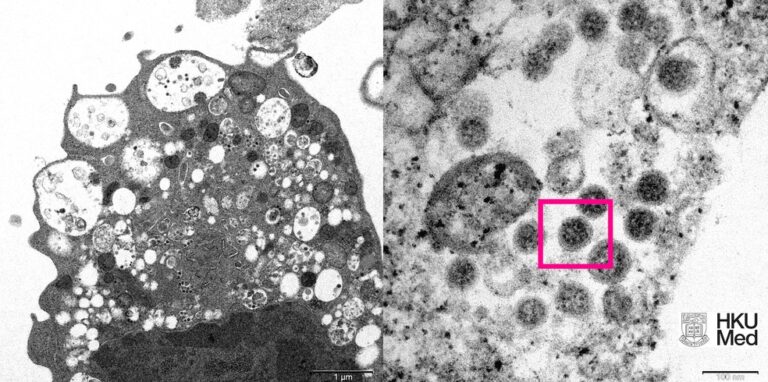

Foto: Cortesia Faculdade de Medicina da Universidade de Hong Kong